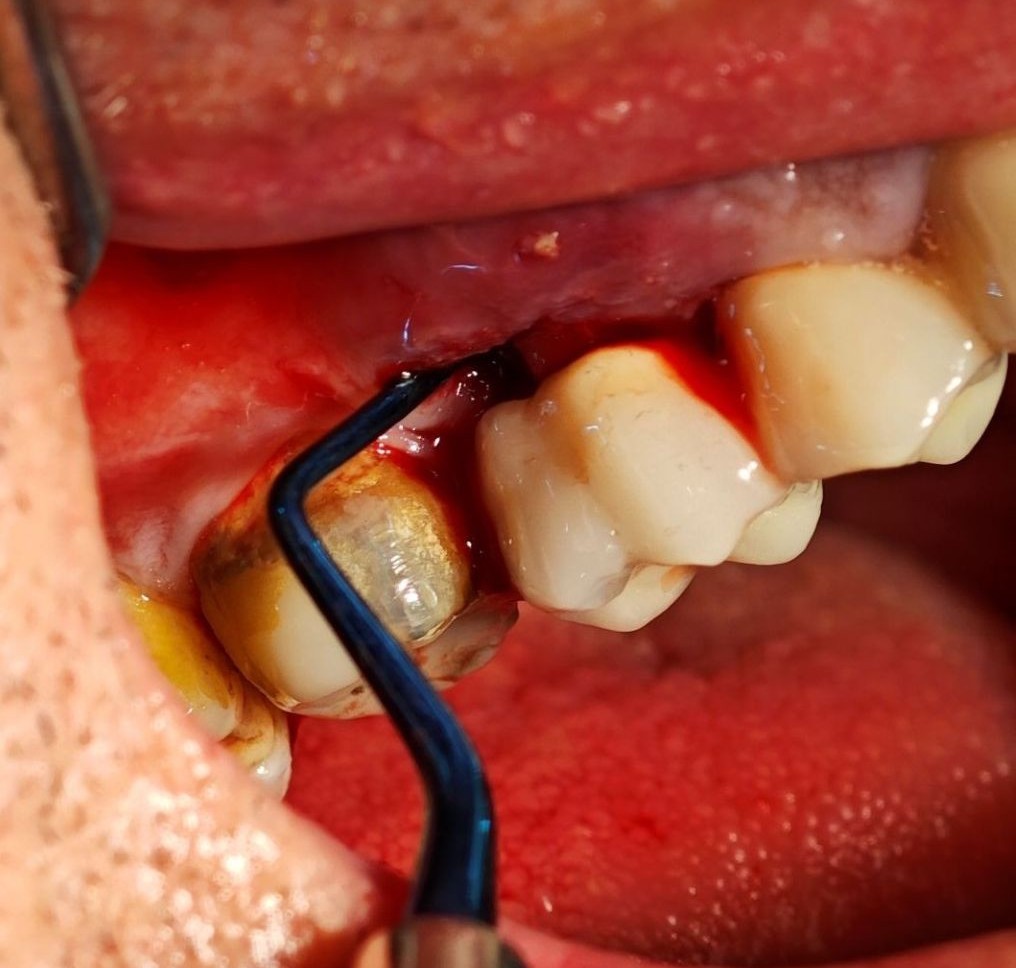

Пародонталната терапија, позната и како пародонтален третман, се однесува на процедури и интервенции насочени кон спречување, дијагностицирање и лекување на болести на пародонтот. Пародонтот се однесува на потпорните структури на забите, вклучувајќи ги непцата, пародонталниот лигамент, цементот и алвеоларната коска. Пародонталната терапија првенствено е фокусирана на лекување на пародонталната болест, која е воспалителна состојба која ги зафаќа непцата и околните ткива. Најчестиот облик на пародонтална болест се нарекува периодонтитис, кој се карактеризира со прогресивно уништување на пародонталните ткива. Ако не се лекува, периодонтитисот може да доведе до губење на забите. Ласерско контурирање на гингивата, исто така познато како контурирање на непцата или преобликување на непцата, е стоматолошка процедура која користи ласерска технологија за модифицирање и преобликување на линијата на непцата. Станува збор за козметичка процедура која има за цел да го подобри изгледот на насмевката преку создавање на побалансирана и пропорционална линија на непцата.